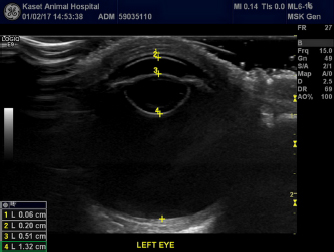

An immersion ultrasound A-scan biometry (Axis II PR, Quantel Medical, France) was carried out to determine the axial length (AL) and the IOL dioptric power calculation (Fig. 3). Anesthesia was carried out using intramuscular 2.5 mg/kg tiletamine–zolazepam (Zoletil, Virbac Laboratories, Carros, France), followed by topical anesthesia with 0.5% tetracaine hydrochloride (Alcon®, Alcon-Couvreur, Puurs, Belgium). The scleral immersion shell, which was filled with normal saline, was placed on the cornea and positioned parallel to the axis of the eye. The average ALs were 21.54 mm OD and 21.22 mm OS (Fig. 4). The refractive powers of the IOLs were +25.48 diopter OD and +25.97 diopter OS and were calculated based on the SPK-2 formula (Table 1). Since this orangutan was quite young, corneal flattening and increasing AL would be expected when growing up (Flitcroft et al., 1999). The chosen IOL dioptric power was 20% subtraction from the calculated dioptric power from the SPK-2 formula to avoid the development of high myopia. Therefore, IOLs with +23.5 diopter OD and +24 diopter OS were prepared for this surgery.

Fig. 4. A-scan biometry included anterior chamber (AC), Lens (L), vitreous (V), and average (AL) being displayed on the screen of the ultrasound both OD (a) and OS (b).